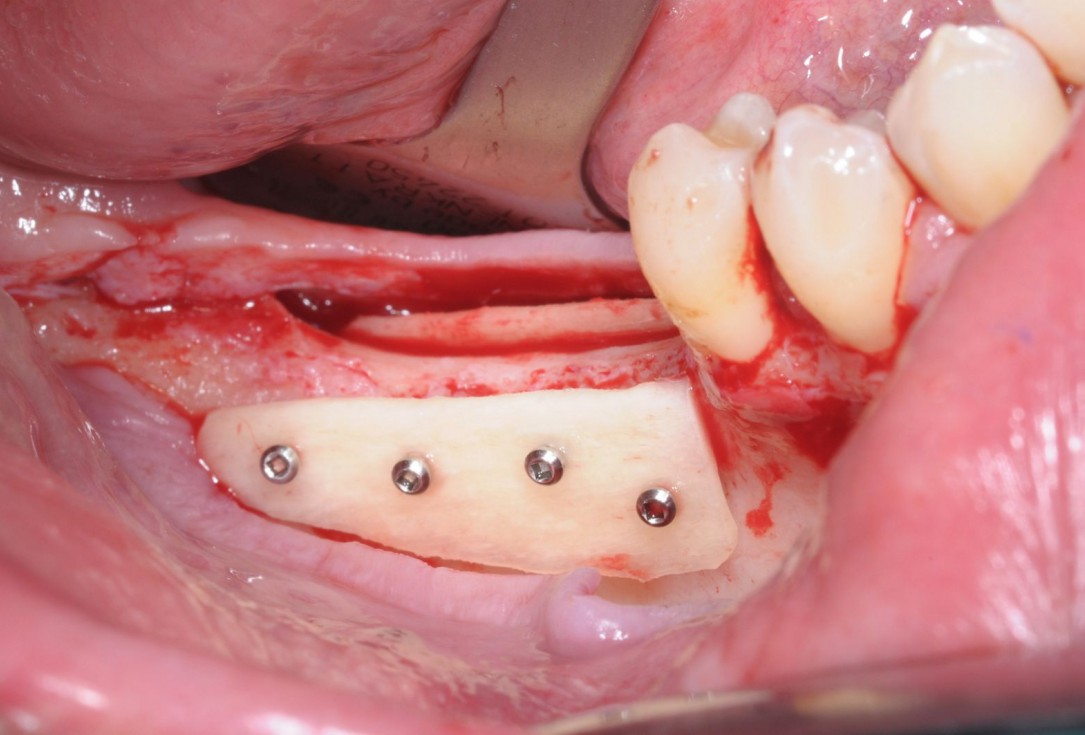

06/28 - Fixation of two defect-adapted maxgraft® cortico plates with osteosynthesis screwsThree-dimensional augmentation with maxgraft® cortico - Dr. R. Würdinger